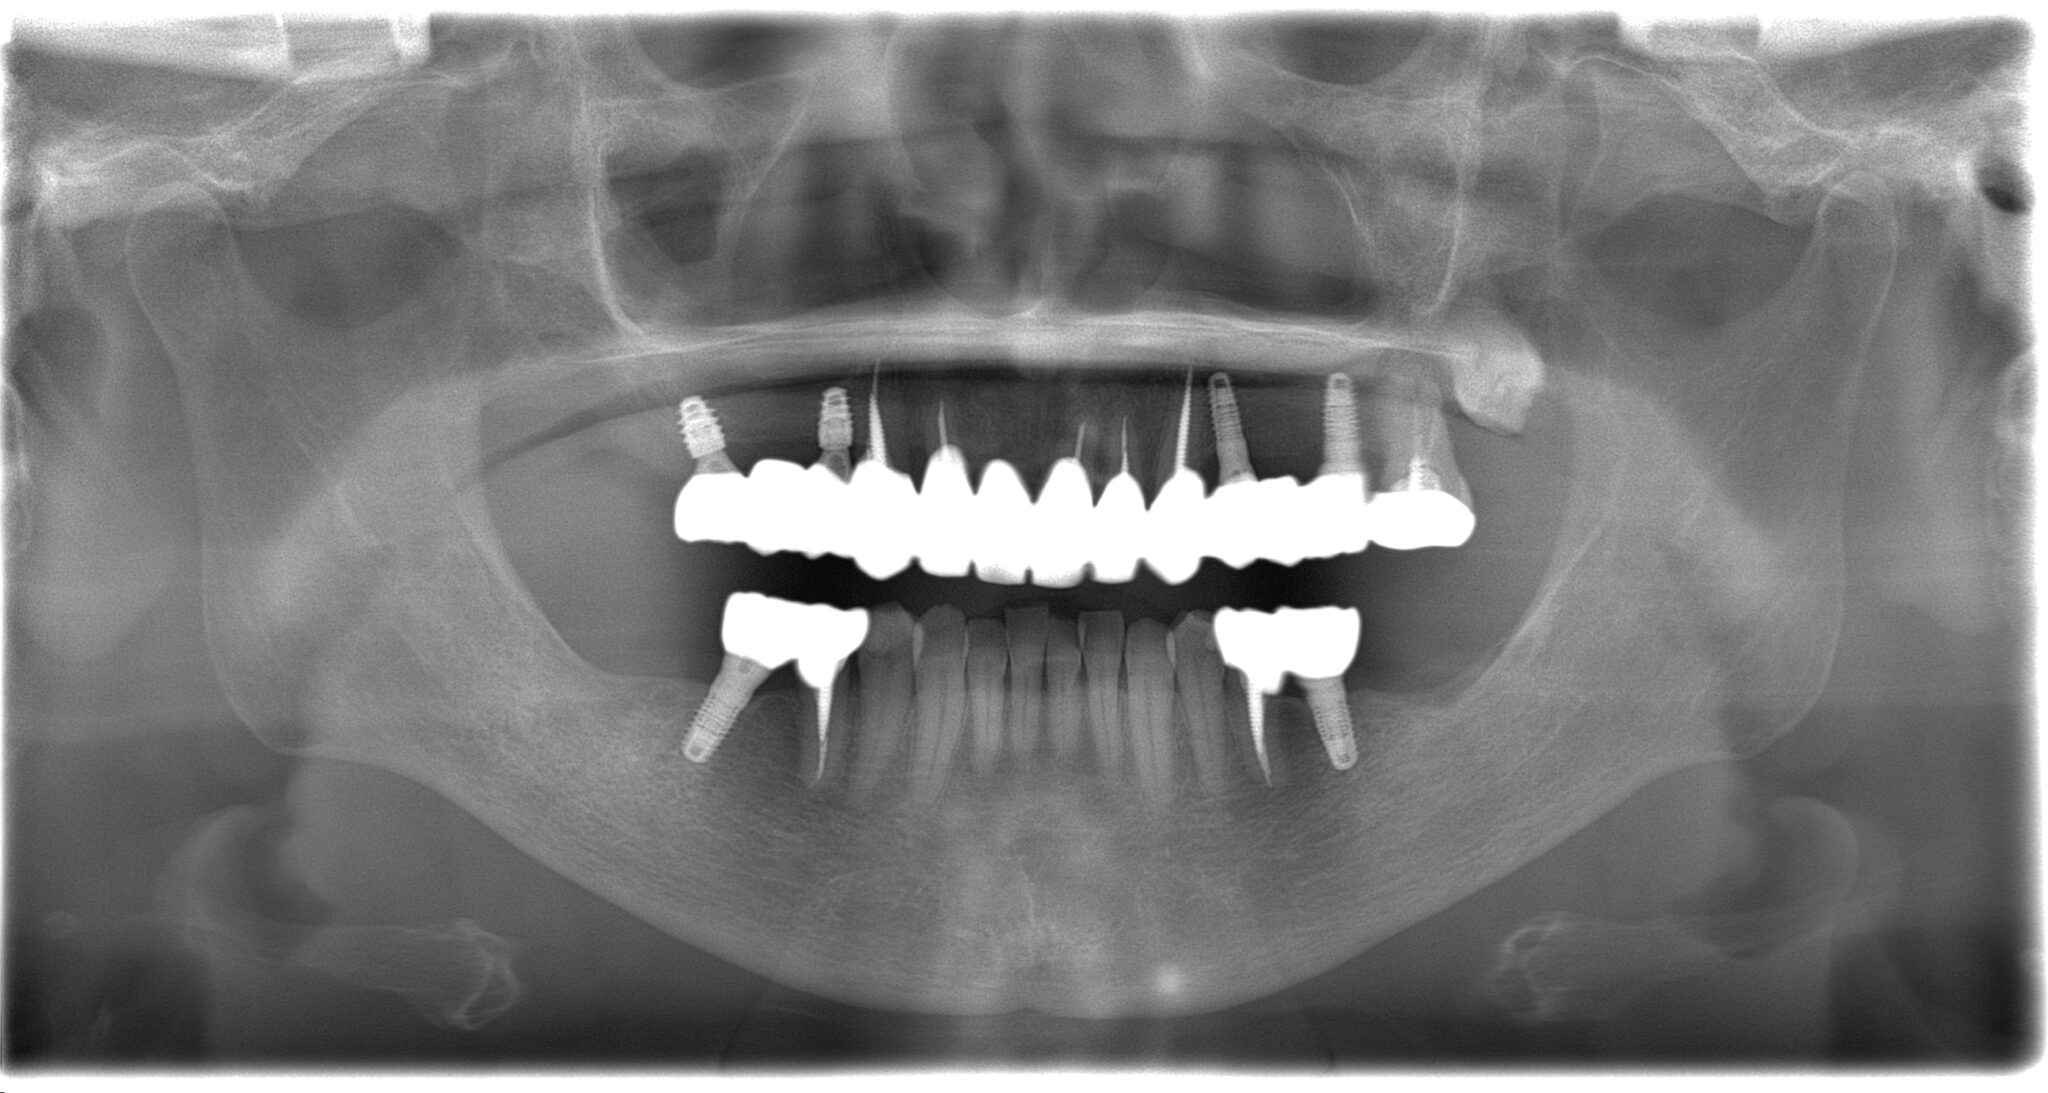

全顎治療症例

| 治療内容 | インプラント埋入(右上4・6,左上4・6,右下6,左下6) ジルコニアBr(右上3―左上3) ジルコニア(右下5,左下5) |

インプラント 1年5ヶ月/13回 ジルコニアBr、ジルコニアクラウン 3ヶ月/10回 |

| 費用 | インプラント: 2,552,000円 その他治療: 640,000円 合計 3,192,000円 *いずれも税込 |

- リスク・副作用

- 定期的なメインテナンスを行わない場合、インプラントが脱落する可能性があります。被せ物は経年的な劣化で欠ける可能性があります。